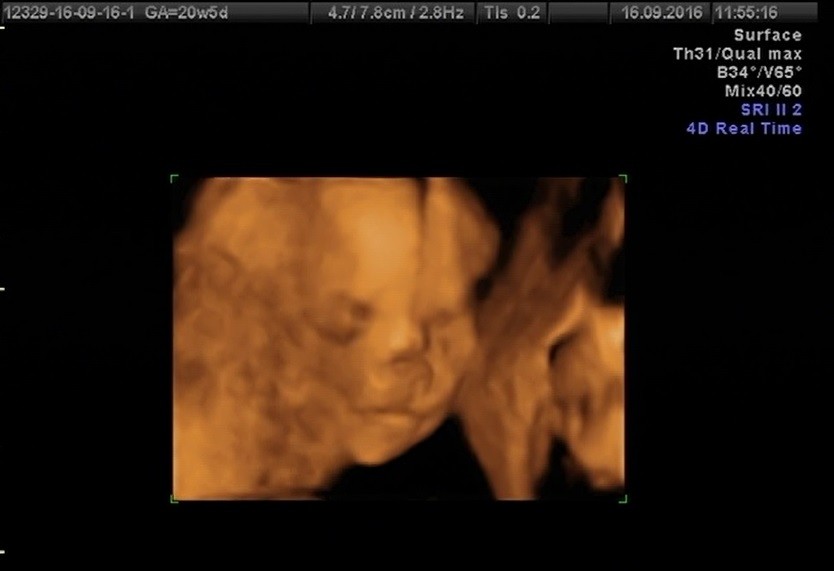

Ja już po badanku. Wszystkie parametry w normie. Dzidzia rośnie, waga 363g. Pan doktor powiedział, że między nogami widzi hamburgera, więc wygląda na dziewczynkę :) Miałam również mierzoną szyjkę przez brzuch i dopochwowo, 49mm i wszystko ładnie pozamykane, więc nie powinno być z tym problemu.

A to moja dzidzia:

Hej dziewczyny! Dziękuję wszystkim za trzymanie kciuków, jesteście kochane, nawet nie macie pojęcia ile daje takie duchowe wsparcie:)